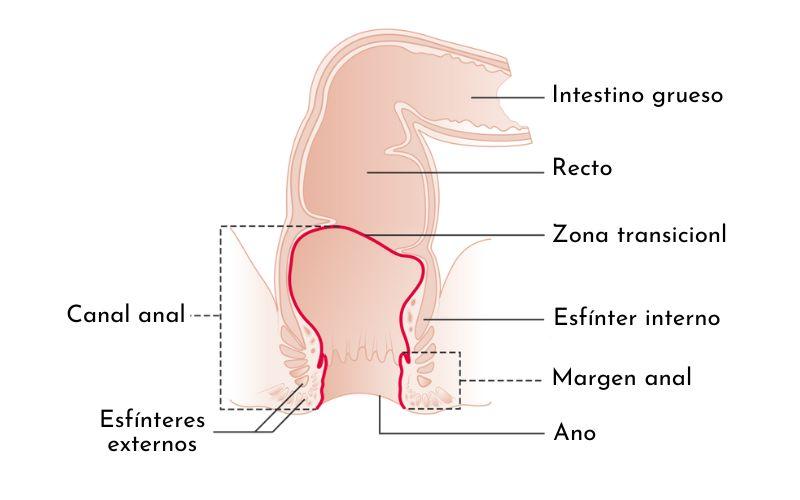

- Anatomía. El intestino grueso, conocido como colon, es la porción del aparato digestivo que continúa al intestino delgado. Tiene forma de marco y está compuesto por una parte ascendente, una transversal y una descendente. El recto es la última porción del aparato digestivo antes de alcanzar el canal anal, que finalmente expulsa el excremento al exterior. Es redondo, se ubica justo después del colon y mide entre 10 y 12 cm. En el recto hay tres repliegues mucosos que se conocen como válvulas de Houston, o válvulas anales. En la mayoría de las personas hay dos válvulas izquierdas y una derecha. Sin embargo, se han descrito casos de individuos que presentan solo 2 válvulas. La primera válvula de Houston se encuentra entre 11 y 13 cm del ano, la segunda está ubicada a 8 cm del ano, y es la única del lado derecho. La última válvula también se conoce como válvula de Kohlrausch, la cual está a 6 cm del ano. La última válvula de Houston, que se encuentra más cerca del canal anal, es la más prominente. Por ese motivo, es la única que se identifica fácilmente en los estudios radiológicos especializados. Anatómicamente, esta válvula divide al recto en una porción superior y una inferior.

- Histología. El recto es la porción del tubo digestivo que continúa al colon. Su conformación celular es casi idéntica a este. En su estudio macroscópico se observan cuatro estratos o capas, que son: mucosa, sub-mucosa, muscular y serosa. La capa mucosa tiene células de tipo cilíndrico simple. Esto quiere decir que posee una sola capa de células altas y redondas. Las válvulas de Houston son repliegues mucosos, por lo tanto, sus células son también cilíndricas simples. A pesar de que las válvulas de Houston son pliegues formados por mucosa, en estudios microscópicos especializados se ha encontrado que contienen fibras musculares lisas. Raramente, están compuestas de epitelio mucoso y sub-mucoso únicamente. La capa sub-mucosa es donde se encuentran los vasos sanguíneos y nervios, o paquete vásculo-nervioso. El estrato sub-mucoso también forma parte de la estructura de las válvulas de Houston. La capa serosa es un revestimiento de peritoneo laxo que cubre los órganos intra-abdominales. Los dos tercios proximales del recto se encuentran cubiertos con serosa, mientras el tercio distal, el más cercano al canal anal, no. La tercera válvula de Houston es la estructura anatómica que marca la división entre los dos tercios superiores y el tercio inferior del recto, es decir, que al nivel de esta válvula el recto se divide en una porción cubierta con serosa y una porción descubierta.